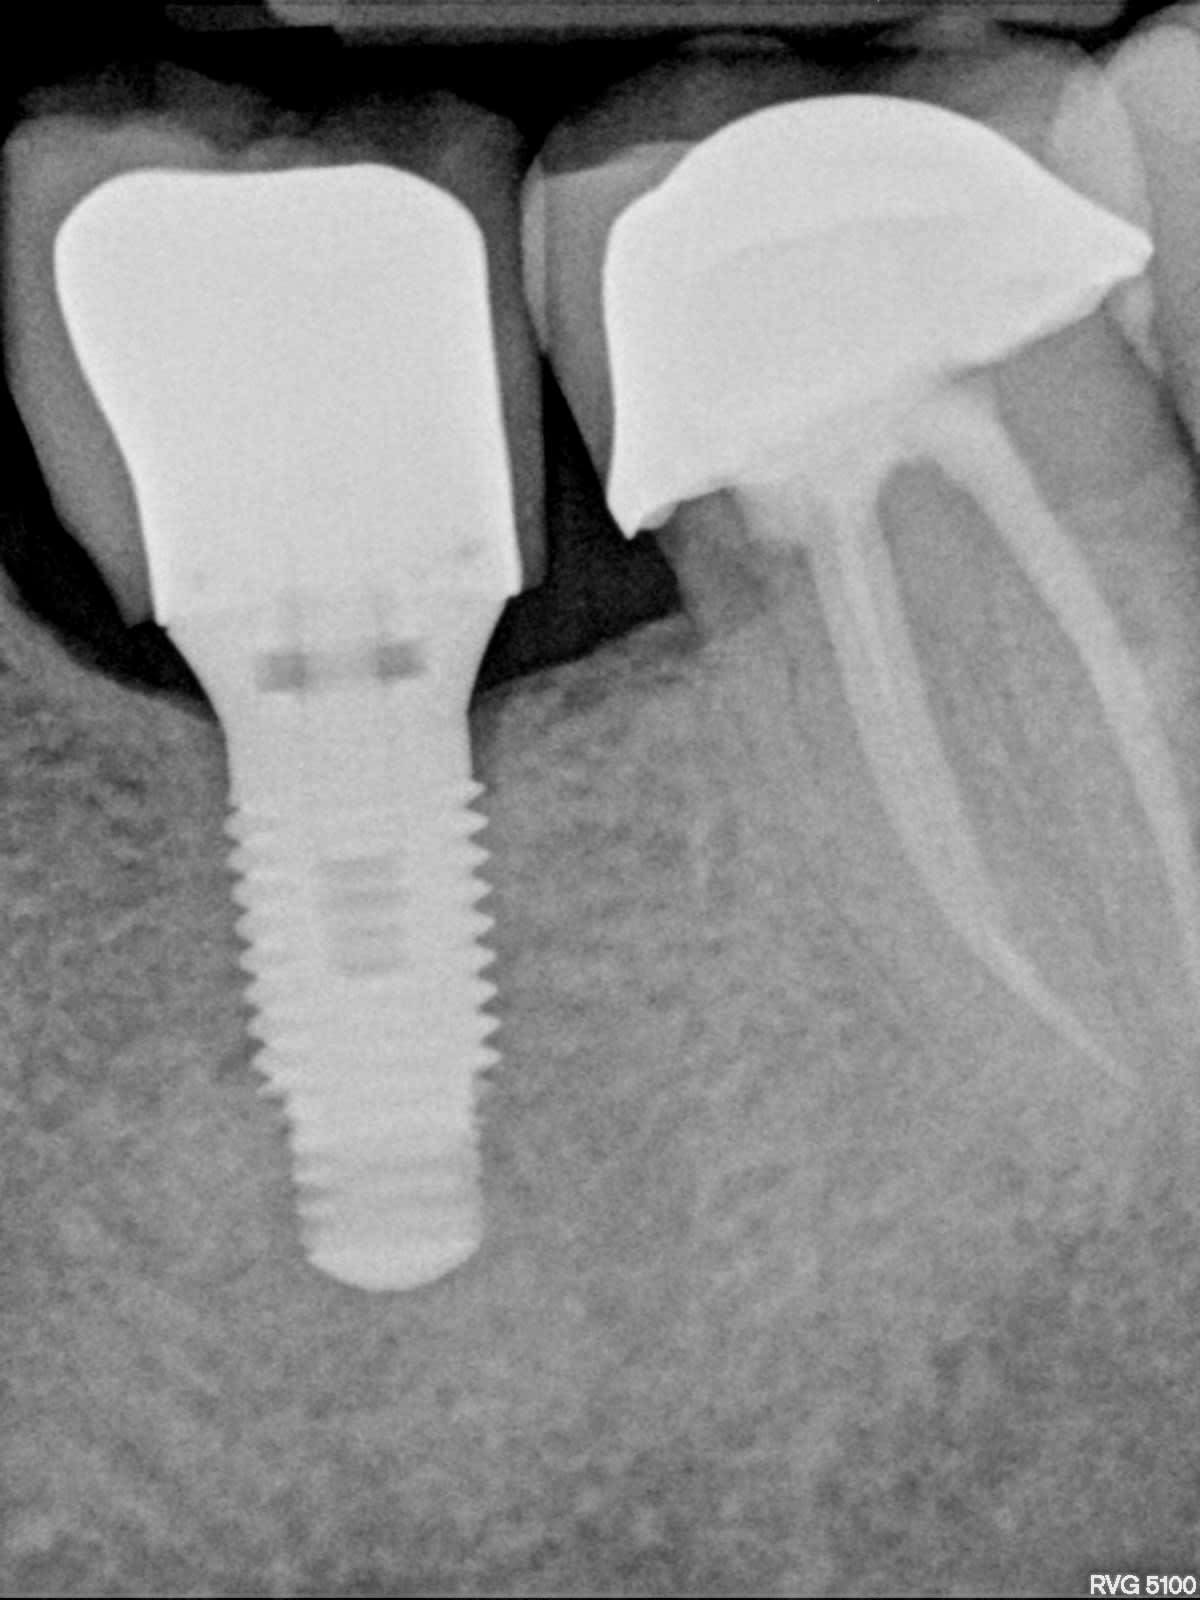

IMPLANT EN 36?

Je pense que les trois sont les mêmes, posés en France en un temps.

ZIMMER TSVM?

Alors zimmer, oui, 100%

Mais pour le coup je pencherais pour des advent car l’évasement au col et la hauteur du filetage de la connexion et de la vis me font plus penser à cet implant tissue level qu’au classique TSV qui lui est un bone level